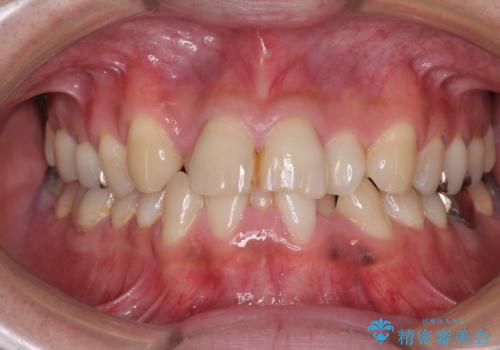

重なって磨きにくい上下の前歯 ワイヤー装置での抜歯矯正

- 前歯のデコボコを改善したいと来院された患者様です。

口元の突出感はないものの、上顎前歯のデコボコが著しかったため、上下顎左右小臼歯4本を抜歯することとしました。

上下の正中位置を改善するため、右下は第一小臼歯を、その他は第二小臼歯を抜歯することとしました。